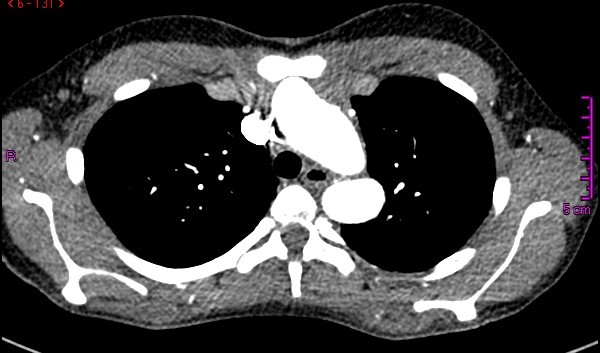

Figure 1. Cross-sectional CT angiogram view of the thorax, where a dilated aortic arch near the origin of the supraaortic vessels is observed in close proximity to the sternum.

A 14-year-old female patient with clinical features of Loeys-Dietz syndrome presented to the authors’ institution with new onset atypical chest pain. The patient related a prior surgical correction of an ascending aorta aneurysm at 18 months of age, in addition to a sibling who had an ascending aorta aneurysm surgically corrected in early childhood. Transthoracic echocardiography showed a tricuspid aortic valve with mild insufficiency, dilation of the aortic root, and dilation at proximal and distal anastomosis of the ascending aorta Dacron tube, without stenosis. Supraaortic vessels showed a tortuous and dilated origin. Given the technical difficulty for surgical correction, computed tomography (CT) angiography of the thoracic aorta was requested with 3D reconstruction for surgery planning. This demonstrated postsurgical inflammatory changes, supraaortic vessels only 2 mm from the sternum, aneurysmal dilatation of the aortic root, ascending aorta, and aortic arch, tortuosity and dilatation of supraaortic vessels, aberrant right subclavian artery, and a normal descending aorta (Figures 1 and 2). A surgical plan was established and was followed throughout the operation by the entire team: